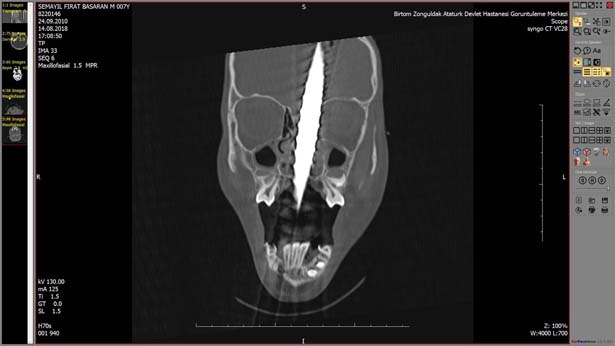

Zonguldak'ta, bisikletiyle gezerken 2 metre yükseklikten düşen 7 yaşındaki Fırat Başaran'ın ağzından giren demir başından çıktı. Yaralı çocuk, ekipler tarafından Bülent Ecevit Üniversitesi Uygulama ve Araştırma Merkezine sevk edildi. Beyin cerrahisi, kulak burun boğaz, plastik cerrahisi, anestezi ve AFAD ekipleri başarılı bir ekip çalışması sonucunda 6 saat süren operasyonla 1 metre uzunluğundaki demir çubuk operasyonla alındı. Çocuk yoğun bakım ünitesine kaldırılan 7 yaşındaki Fırat Başaran'ın tedavisi devam ediyor.

İlk günlerin büyük önem taşıdığını ifade eden Beyin ve Sinir Cerrahisi Anabilim Dalı uzmanı Doç.Dr. Şanser Gül ise, "Hastamızı ilk olarak Atatürk Devlet Hastanesinde beyin cerrahisi uzmanı operatör Dr. Emrah Keskin görüyor ve durumu bize haber veriyor. Biz hazırlığımızı yaptık. Temel prensip ilk önce zarar vermeme, üst damaktan ağız içinden giren ve yaklaşık 1 metre uzunluğundaki demir çubuk kafatasını delerek sol ön fontelden 40 santim dışarı çıkmıştı. AFAD ekipleri tarafından 3 santim kalana kadar kesildi. Temel prensiplere bağlı kalarak parçalanan bölgeyi genişleterek demir çubuk rahatlatıldı. Sonra ameliyata alınarak demir çubuk çıkartıldı. Ön beyin düşünce davranışlarımızı yönlendirir; hafıza, düşünme, karar verme, idare etme gibi durumları evet çocuğumuz şu an yoğun bakımda bilinci açık bir şekilde zaman içinde neyi kaybettiğini görmüş olacağız. İlk günlerde hayati önem taşıyan bir durum var o da enfeksiyon ekip olarak tüm işlemler yapıldı. Antibiyotik tedavisine başlandı. İlerleyen günler her türlü sonuca açık" şeklinde konuştu.